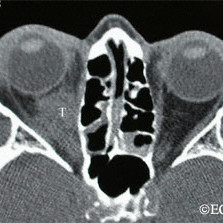

Orbital lymphoma

Orbital lymphoma 6 months after external beam radiation therapy (arrow)

Orbital lymphoma before radiation therapy (T)